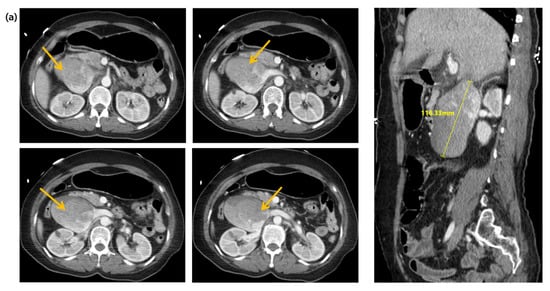

Figure 1.

Computed tomography images of the abdomen and pelvis in (a) the axial and sagittal planes, and (b) the coronal plane. Arrows indicate an inferior vena cava aneurysm.

A 58-year-old woman with an unremarkable medical history visited the emergency department (ED) for worsening dizziness and dyspnea, noted one day before. The patient was alert and had normal peripheral oxygen saturation (SpO2) when the paramedics arrived. However, her mental state and oxygen saturation level declined during transport to the hospital. She had an SpO2 of 83% despite receiving 100% oxygen supplementation through a face mask with a reserve bag. The blood pressure was not measured due to a weak pulse. The patient was drowsy upon arrival at the ED. Cardiac arrest with pulseless electrical activity occurred after five minutes, and spontaneous circulation was restored after two minutes of cardiopulmonary resuscitation. A computed tomography (CT) of the brain, chest, and abdomen–pelvis (AP) was taken two hours after arrival. The AP-CT revealed an 8 × 11 cm saccular aneurysm involving the left and right renal veins at the infrahepatic level of the IVC (Figure 1). The chest CT revealed massive pulmonary embolisms involving both distal main pulmonary arteries (Figure 2a). A hyperdense middle cerebral artery (MCA) sign indicating thrombosis of the M1 MCA segment and widely decreased gray matter densities in the left hemisphere and right frontal lobe were detected on the brain CT (Figure 2b) [5]. A tissue plasminogen activator was administered two and a half hours after arrival, and the patient was admitted to the intensive care unit. The patient developed a seizure; therefore, a follow-up brain CT was performed after six hours. This showed a broad infarcted area involving most of the cerebrum, except for the thalamus and right occipital lobe. An electroencephalogram taken two days after admission suggested the possibility of brain death, and a bedside transthoracic echocardiography performed on the fourth day of hospitalization showed an enlarged RV with reduced RV systolic function. The patient’s family decided against a further evaluation or advanced treatment; therefore, the patient was conservatively managed at this point. Normal blood pressure was not achieved despite administering high-dose inotropic agents during the seventh day of hospitalization, and the patient died on the eleventh day of hospitalization.